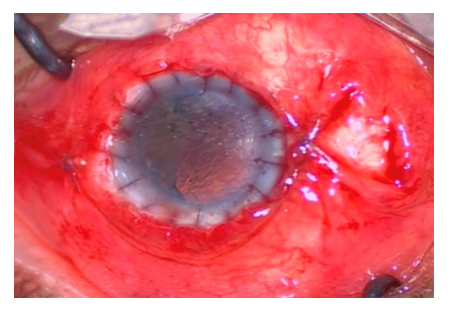

患者的具体治疗过程:入院后于2018年12月1 2号在全身麻醉下行双眼穿透性自体角膜移植+左眼玻璃体切除+左眼晶状体切除+右眼羊膜移植术。手术具体过程为:麻醉满意后常规消毒、铺巾,开睑器开右眼,角膜缘缝合角膜环,标记角膜中心点,用9.5 mm换环钻钻取植床至深板层,沿换钻切口穿刺进前房,黏弹剂分离切口周围虹膜,角膜剪沿环钻切口切除角膜放入湿房作为供体备用;以相同的方法切除左眼角膜。将右眼角膜植片放置在左眼植床上,10-0的尼龙线在1 2、6、3、9点固定,每个钟点间断缝合,松紧适度埋线。将左眼角膜植片放置在右眼植床上,10-0的尼龙线在1 2、6、3、9点固定,每个钟点间断缝合,松紧适度埋线,羊膜平铺于角膜面,10-0尼龙线固定羊膜于角巩膜缘后3 mm,右眼术毕。左眼角膜缘后3.5 mm建立三通道玻璃体切除套管,置灌注管,见玻璃体腔内晶状体,视网膜呈高度近视性改变,行玻璃体及晶状体切除,术毕拔除套管,缝合切口,维持眼压正常。手术顺利,术后予双眼妥布霉素地塞米松眼膏包盖,苏醒安返病房(图3,4 )。术后第1天,左眼视力:手动/眼前;左眼结膜充血,角膜移植片平整,角膜水肿,缝线松紧适度,前房清,稍浅,瞳孔清晰可见,直径约4 mm,瞳孔区透明。术后第9天,左眼结膜轻充血,角膜移植片平整,缝线松紧适度,荧光素钠染色点状着色,前房清,稍浅,瞳孔清晰可见,直径约4 mm,瞳孔区透明;右眼结膜充血,移植片与植床对合好,植片中央溶解状;患者因右眼植片中央溶解,可能导致角膜穿孔,于2018年12月21号行右眼结膜瓣遮盖术。术后21 d患者出院,体格检查:左眼视力:指数/40 cm;左眼结膜轻充血,移植角膜透明,已上皮化,与植床对合良好,缝线在位,前房清;右眼结膜充血,结膜瓣遮盖部分角膜,移植角膜在位,与植床对合良好,缝线在位,中央呈溶解状。患者出院后因家庭偏远未能定期复查,故未能观察患者后续恢复情况。

20230519162259_8944.png

图3 术后左眼图片

Figure 3 Postoperative image of the left eye